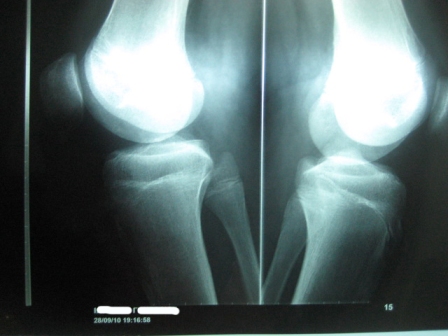

Σύνδρομο Osgood-Schlatter σε νεαρό αθλητή |

Ακτινογραφία 6-10-2009 |